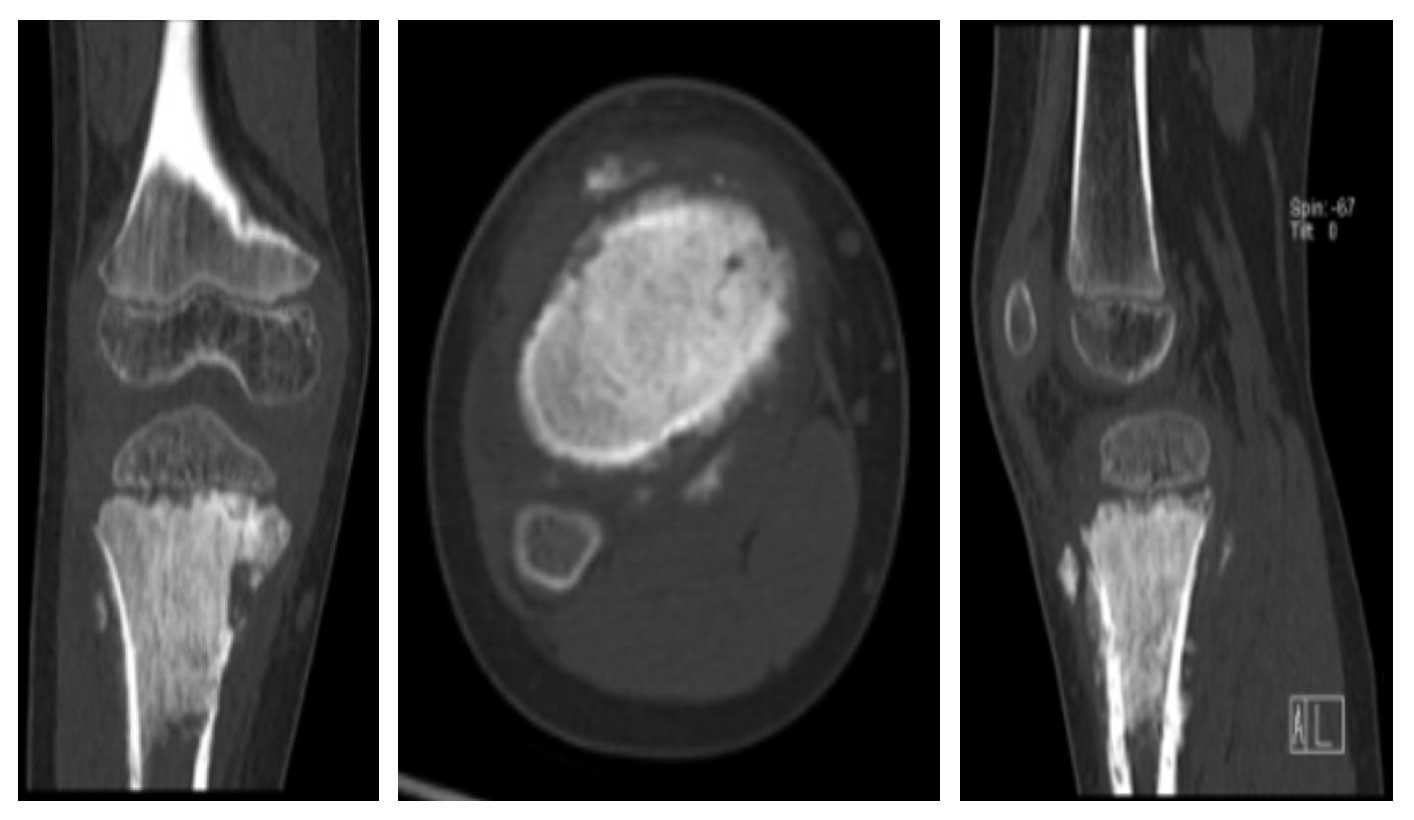

Ameliyat Öncesi: Tomografide aynı lokalizasyonda kemikte harabiyet ve yumuaşak dokuya uzanım görülmekte.